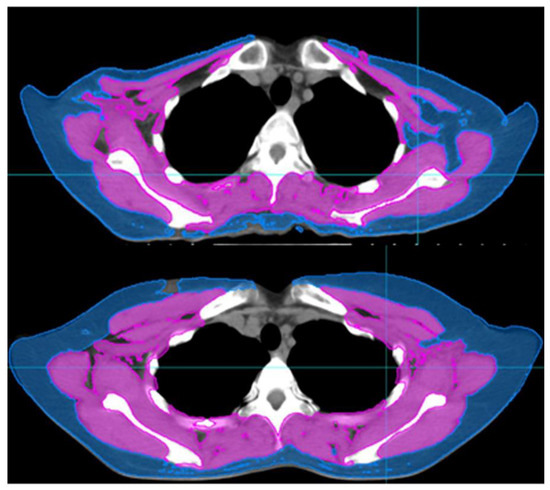

2.2. Measurement of Body Composition and the Definition of Skeletal Muscle Loss